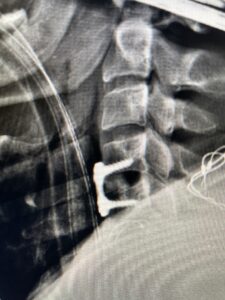

Fig. 3 Intraoperative lateral cervical X-Ray demonstrating C4-5 ACDF

Fig 5. Intraoperative Lateral Cervical X-Ray demonstrating C5-6 ACDF

This 47-year-old male who four months prior was lifting weights developed sharp pain in his neck. After that he developed progressive numbness in his arms, neck pain and headache. He said that the right arm was worse than the left. On examination the patient had long tract weakness on the right side which included his triceps, finger extensors, hip flexors, and dorsiflexors. The patient did not have hyperreflexia. MRI (Fig. 2) demonstrated a massive, extruded disc herniation with severe cord compression. The patient because of progressive myelopathy and spinal cord compression was indicated for anterior cervical discectomy and fusion at C4-5 (Fig. 3). Patient had significant improvement of weakness and numbness post operatively.

This 36-year-old female who had a long history of neck pain had a history on MRI of a C5-6 bulge. She recently after diving into a pool (not hitting her head on bottom) developed progressive problems with her arms. She had developed spontaneous shocks going down her arms and in the back of her neck. Spontaneous shocks going down the neck and spine is called a Lhermitte’s phenomenon and can occur with spinal cord compression and also with multiple sclerosis. On examination, the patient had long tract weakness of her arms, right greater than left. Her finger extensor weakness was profound on the right. MRI (Fig. 4) of the cervical spine revealed a massive C5-6-disc herniation causing significant cord compression right greater than left with subtle cord signal change. Because of the severe myelopathy, the patient was indicated for surgery. A C5-6 anterior cervical discectomy and fusion was performed (Fig. 5). The patient had a dramatic improvement of her strength in the recovery room.